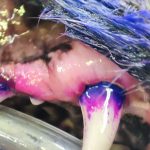

ここを歯科レントゲン撮影してみると、乳歯が溶けかけて残って炎症をおこしていました。

ここを歯科レントゲン撮影してみると、乳歯が溶けかけて残って炎症をおこしていました。